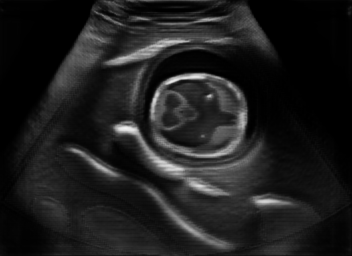

US simulation. We used a ray-tracing framework to render B-mode images from a geometric fetal model, by simulating a convex probe placed at multiple locations and orientations on the abdominal surface, with imaging settings listed in Tab 1. At each location, simply rasterizing a cross-section through the triangulated anatomical surfaces at the ultrasound center imaging plane provided corresponding semantic maps. Fig. 3 shows example B-mode images with corresponding semantic maps. A total of simulated frames were resized to and randomly split into training-validation-test sets by 80-10-10%.